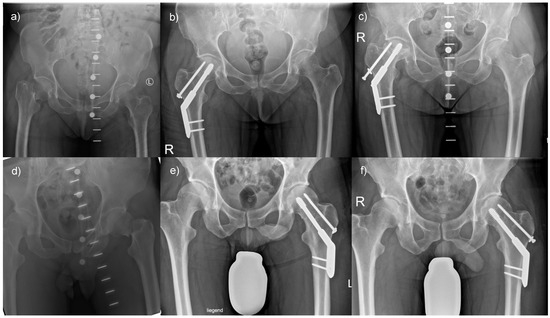

Only a few patients had complications when treating their femoral neck fracture with a DHS with an anti-rotational screw. For example, a 57-year-old female patient was transferred to our hospital following a fall from standing height. She had a Pauwels type 3, Garden type 4 fracture (Figure 5a) and was treated with a DHS with an anti-rotational screw (Figure 5b). Despite an initially satisfactory follow-up, she presented with an avascular necrosis of the femoral head six months following surgery (Figure 5c), which required conversion to total hip arthroplasty. However, most patients treated with a DHS with an anti-rotational screw had a satisfactory outcome. For instance, a 40-year-old male patient also presented with a Pauwels type 3, Garden type 4 fracture (Figure 5d) and received a DHS with an anti-rotational screw (Figure 5e). The follow-up result was inconspicuous, and the fracture healed (Figure 5f).

Figure 5.

Outcomes of femoral neck fractures when treated with a DHS with anti-rotational screw: (a) A 57-year-old female patient presented with a highly unstable femoral neck fracture, (b) which was treated with a DHS with an anti-rotational screw, but (c) developed an avascular necrosis of her hip. In comparison, (d) a 40-year-old male patient presented with a comparable fracture morphology, (e) underwent analogous treatment, and (f) demonstrated favorable postoperative results.

A minority of patients had complications when femoral neck fractures were treated with an FNS. A 67-year-old male patient was transferred to our hospital following a fall from standing height. He had a Pauwels type 2, Garden type 3 fracture (Figure 6a) and was treated with an FNS (Figure 6b). Despite an initially satisfactory follow-up, he presented with a consecutive cutting-out of the implant at six months following surgery (Figure 6c). However, most patients treated with an FNS had a satisfactory outcome. For instance, a 62-year-old male patient presented with a Pauwels type 2, Garden type 2 fracture (Figure 6d) and received an FNS (Figure 6e). The follow-up result was inconspicuous, and the fracture healed (Figure 6f).

Figure 6.

Outcomes of femoral neck fractures when treated with an FNS: (a) A 67-year-old male patient presented with an unstable femoral neck fracture, (b) which was treated with an FNS, but (c) presented with implant cut-out following surgery. In comparison, (d) a 62-year-old male patient presented with a comparable fracture morphology, (e) was treated in the same manner, and (f) had a favorable postoperative outcome.